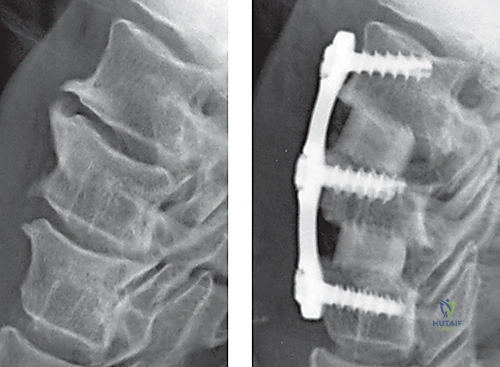

- الأشعة السينية (X-rays): لتقييم الهيكل العظمي والاصطفاف الفقري.

الخطوة 7: التثبيت المعدني (Instrumentation)

لضمان الاستقرار الفوري ومنع حركة الطعم العظمي حتى يكتمل الالتحام (والذي يستغرق أشهراً)، يقوم الدكتور هطيف بتثبيت شريحة معدنية صغيرة من التيتانيوم على الجزء الأمامي من الفقرتين باستخدام براغي دقيقة.